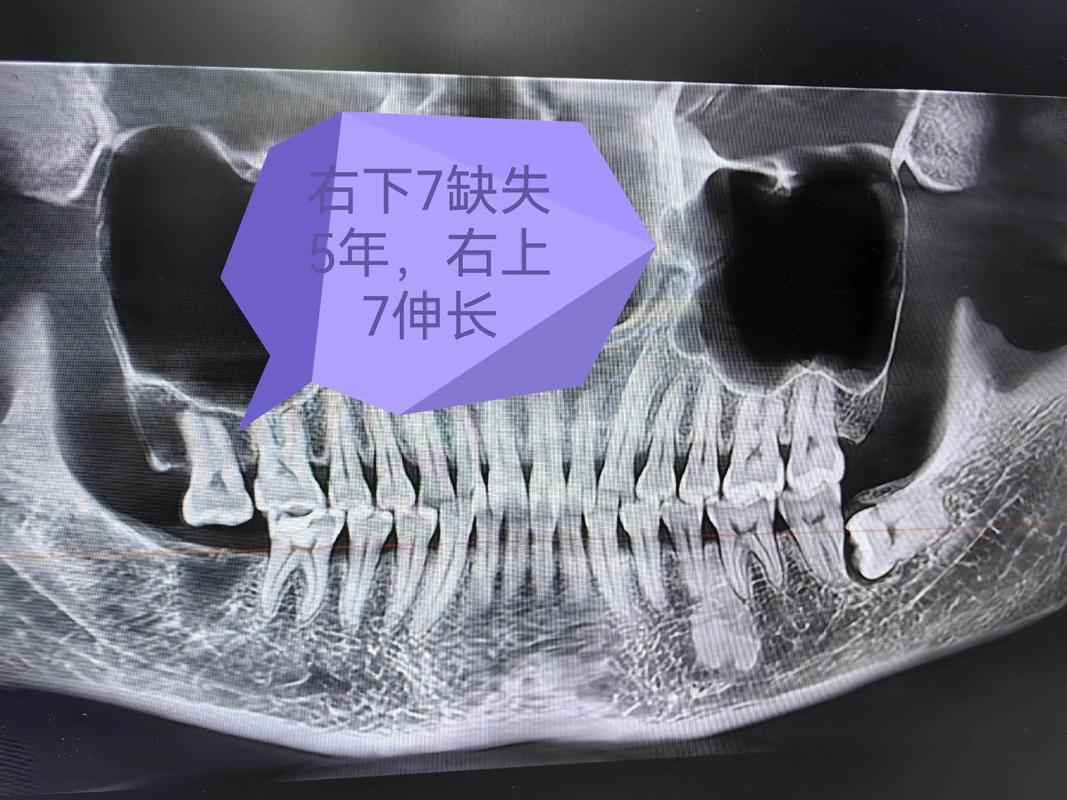

注意事项:术前需拍摄CBCT,明确牙根位置和骨量;加力时需监测牙根吸收情况,定期拍摄根尖片。